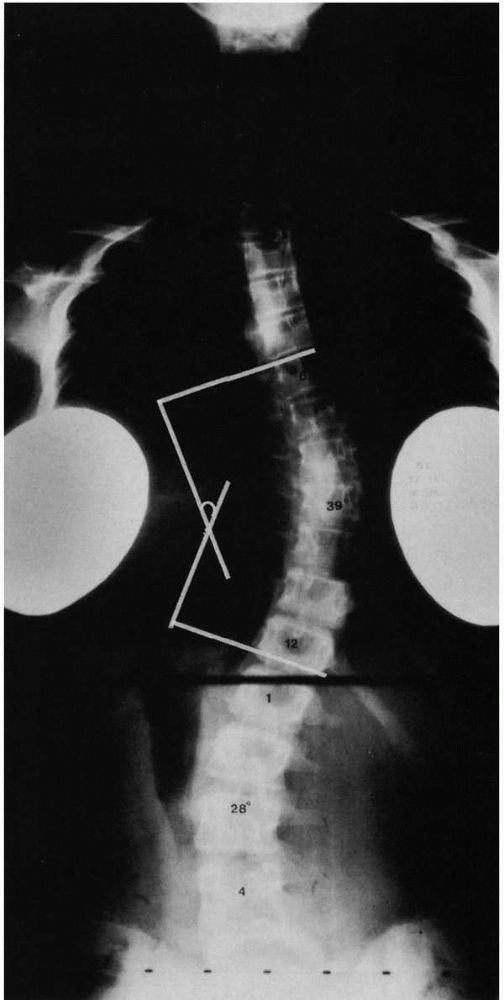

![]() |

FIGURE 16-5.

Curve measurements (Cobb method). (1) Apparent perpendicular is erected from the endplate of the most caudal vertebrae, whose inferior endplate tilts maximally to the concavity of the curve (inferior end vertebrae). (2) A perpendicular is erected from the end-plate of the most cephalad vertebrae, whose superior end-plate tilts maximally to the concavity of the curve (superior end vertebrae). The curve value is the number of degrees formed by the angle of intersection of these perpendiculars, in this case 39°. |